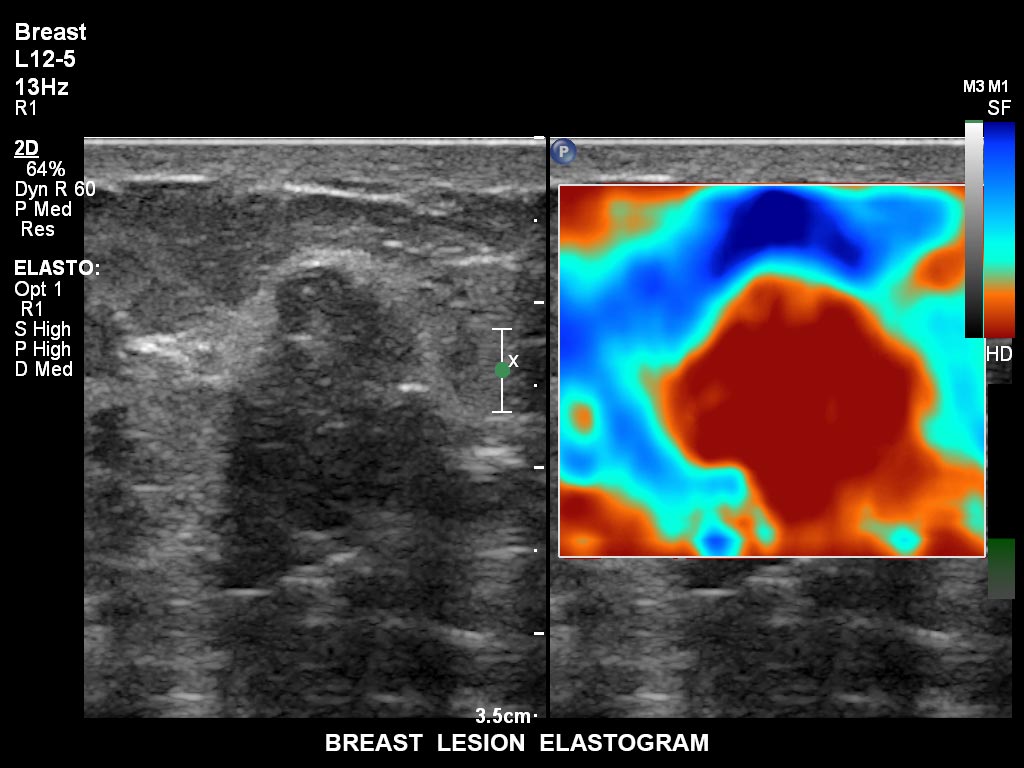

Die EPIQ-Produktreihe mit ausgereiften Schallköpfen erfüllt die Anforderungen auch Ihrer anspruchsvollsten gynäkologischen Untersuchungen und während der gesamten Schwangerschaft.